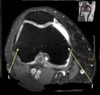

What is letter A?

RT FEMUR

111

What is letter B?

PATELLA

112

What is letter C?

VASTUS MEDIALIS MUSCLE

113

What is letter D?

SARTORIUS MUSCLE

114

What is letter E

MEDIAL EPICONDYLE

115

What is letter F?

MEDIAL HEAD GASTROCNEMUS

116

What is letter G?

LATERAL HEAD GASTROCNEMUS

117

What is letter H?

POSTERIOR CRUCIATE LIGAMENT

118

What is letter J?

119

What is letter L?

LATERAL EPICONDYLE

120

What is letter K?

MEDIAL RETINACULYM

121

What is letter M?

ANTERIOR CRUCIATE LIGAMENT

122

What is letter N?

LATERAL PATELLAR RENTINACULUM

123

What is letter O?

INTERCONDYLAR FOSSA

124

What is letter P?

ARTICULAR CARTILAGE